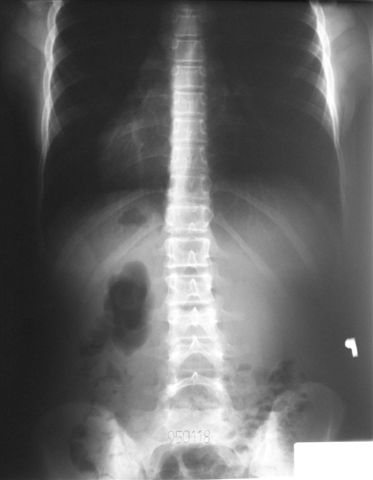

W początkowych skoliozach tzw. idiopatycznych przez specjalny system usprawniania i ćwiczeń, zalecenia rehabilitacyjne można zatrzymać rozwój skoliozy a nawet uzyskać poprawę osi kręgosłupa.

Na radiogramach przebieg leczenia jednej z moich pacjentek.